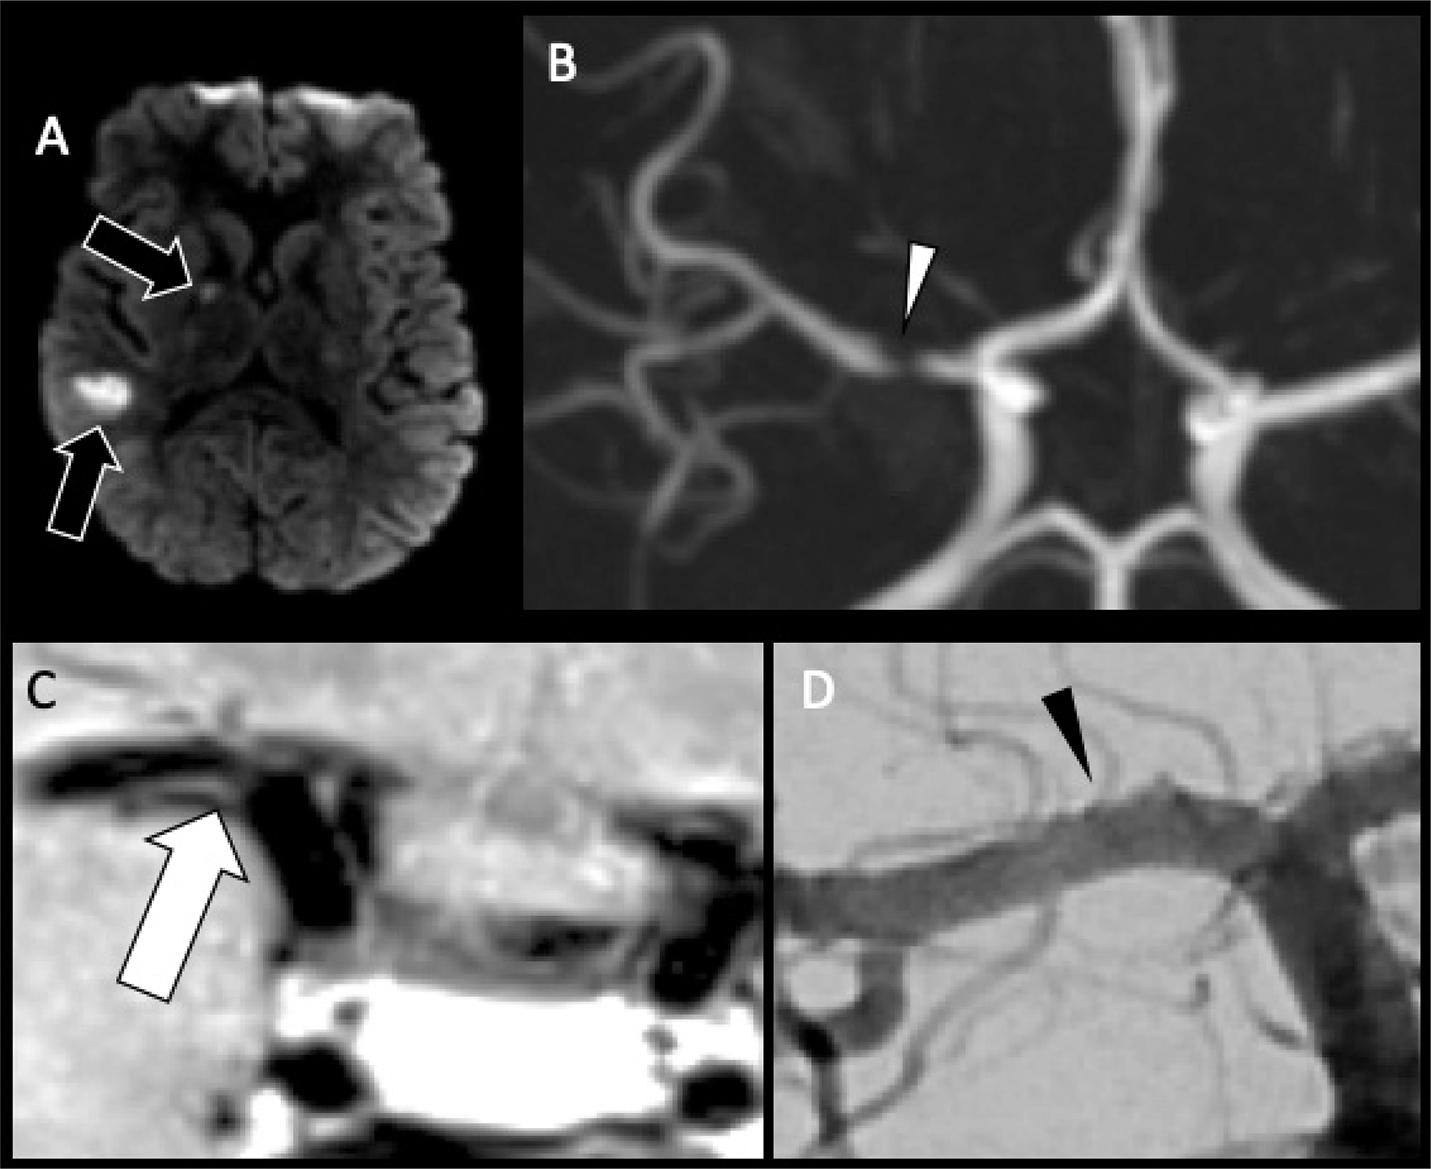

Fig 5

Figure 5. A 13-year-old previously healthy female who presented with new left-sided facial weakness. Diffusion weighted image (A) demonstrate acute infarcts in the right middle cerebral artery (MCA) territory (black arrows). Time-of-Flight MRA (B) shows stenosis of the proximal right M1 MCA segment (white arrowhead). Vessel wall imaging (C) demonstrates a cuff of enhancement at the stenosis (white arrow). Digital subtraction angiography (D) demonstrates a focal arterial irregularity and banding (black arrowhead) resulting in mild stenosis, compatible with focal arteriopathy of a likely inflammatory nature.